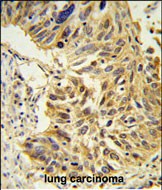

IHC 1/100-1/500 Human,Mouse,Rat